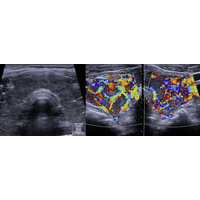

Einer Schilddrüsenüberfunktion können verschiedene Ursachen zugrunde liegen. Zum einen ist dies eine vermehrte Eigenproduktion von Schilddrüsenhormonen bei autonomen Knoten (mit und ohne Vergrößerung der Schilddrüse). Alternativ können Schilddrüsen-spezifische Autoantikörper (TRAK= TSH-Rezeptor-Antikörper bei Morbus Basedow, Abbildung 1, nächste Seite) zu einer dauerhaften Aktivierung des TSH-Rezeptors an den Schilddrüsenzellen führen und anstelle des physiologischen Hormons TSH die Schilddrüsenhormonproduktion aktivieren.

Bei einer Sonografie kann eine Vergrößerung der Schilddrüse mit und ohne Knotenbildung leicht erkannt werden, welche allerdings nicht immer ein Anlass zur Sorge darstellt.

Bei sonografisch nachweisbaren Knoten in der Schilddrüse kann eine Szintigrafie eines radioaktiven Markers die hormonelle Aktivität der Schilddrüse bzw. der Knoten zeigen. Hier können Gewebestellen mit besonders hoher oder geringer Funktion (sog. "kalte" und "heiße" Knoten detektiert werden.

Abbildung 1: Sonografie der Schilddrüse bei Morbus Basedow, die untere Abbildung zeigt die vermehrte Durchblutung mittels Dopplersonografie